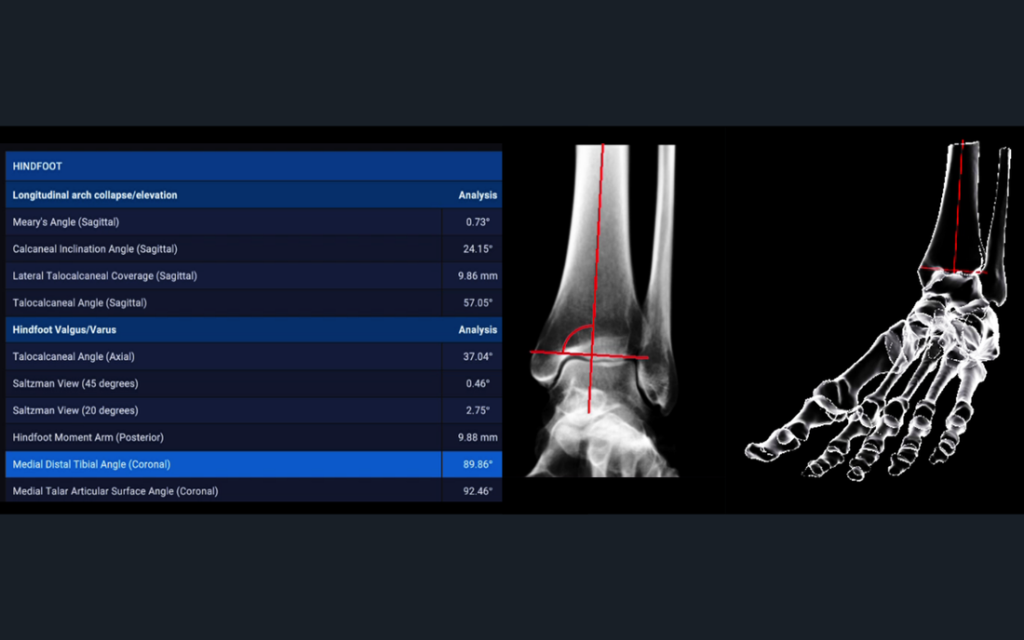

Disior®’s new Bonelogic® Planning module is quick and easy-to-use software that supports you to plan orthopedic treatments of the hand or foot. This product can be purchased together with the Hand & Wrist or Foot & Ankle modules to give you complete control over your clinical workflow.

3D treatment planning in minutes, saving you time in the operation room

Live bone alignment analytics* that help support your decision making